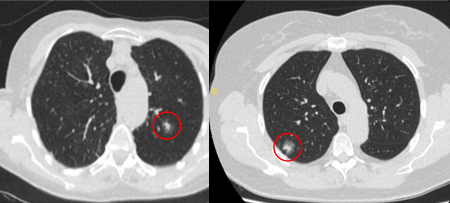

Nódulos semissólidos: o crescimento de um componente sólido sugere a necessidade de considerar uma investigação e/ou tratamento adicionais.[Figure caption and citation for the preceding image starts]: Cortes de tomografia computadorizada (TC) com exemplos de nódulos solitários semissólidosDo acervo de Dr. George Tsaknis, MD, PhD, FRCP (Londres), MRQA, MAcadMEd, PGCert; usado com permissão [Citation ends].